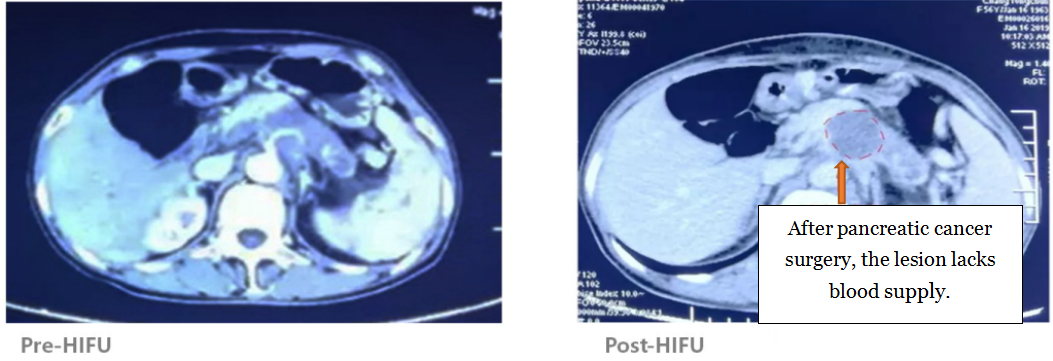

A follow-up CT scan one day after HIFU treatment showed 80% tumor ablation.

Pancreatic Cancer Treatment Case 8:

57 years old, pancreatic cancer

After HIFU treatment, a follow-up CT scan revealed complete ablation at the center of the tumor.